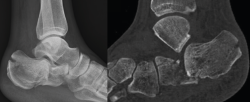

Radiológicamente, se evaluó la reducción conseguida, mediante la medición del ángulo de Böhler poscirugía, y el mantenimiento de dicha reducción midiendo dicho ángulo a los 3 meses poscirugía. El ángulo de Böhler(21) se mide en una radiografía lateral del tobillo tomando la intersección de una línea trazada desde la cara superior de la tuberosidad del calcáneo posterior a la superficie articular subastragalina superior y una línea trazada desde la superficie articular subastragalina superior a la cara superior del proceso anterior del calcáneo (Figura 1). Se considera este ángulo dentro de la normalidad cuando se obtienen unos ángulos entre 20 y 40°, siendo los ángulos < 20° sugerentes de fractura.

Figura 1. Abordaje del seno del tarso de 2-3 cm. Se realiza una línea que va desde el cuarto metatarsiano (4th) al peroné. F: fíbula.